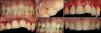

El tercer caso corresponde a un hombre de 28 años de edad. A pesar de existir un buen estado de salud periodontal, el paciente presenta una sonrisa gingival en la que quedan expuestos más de 5mm de encía creando un evidente compromiso estético (fig. 5A). La técnica quirúrgica empleada repite exactamente la misma secuencia del caso 1. En la figura 5B se aprecia el resultado a los 14 días después de la retirada de las suturas y finalmente (fig. 5C) se aprecia el resultado final después de 4 semanas de la intervención, pudiendo observar un resultado estético óptimo en relación con el estado inicial.